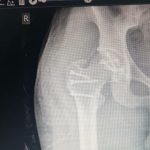

تعويض مفصل زانو و لگن ، جراحى هاى آرتروسكوپى زانو و ترميم رباط صليبى

تعویض مفصل زانو و هیپ

شکستگی ها